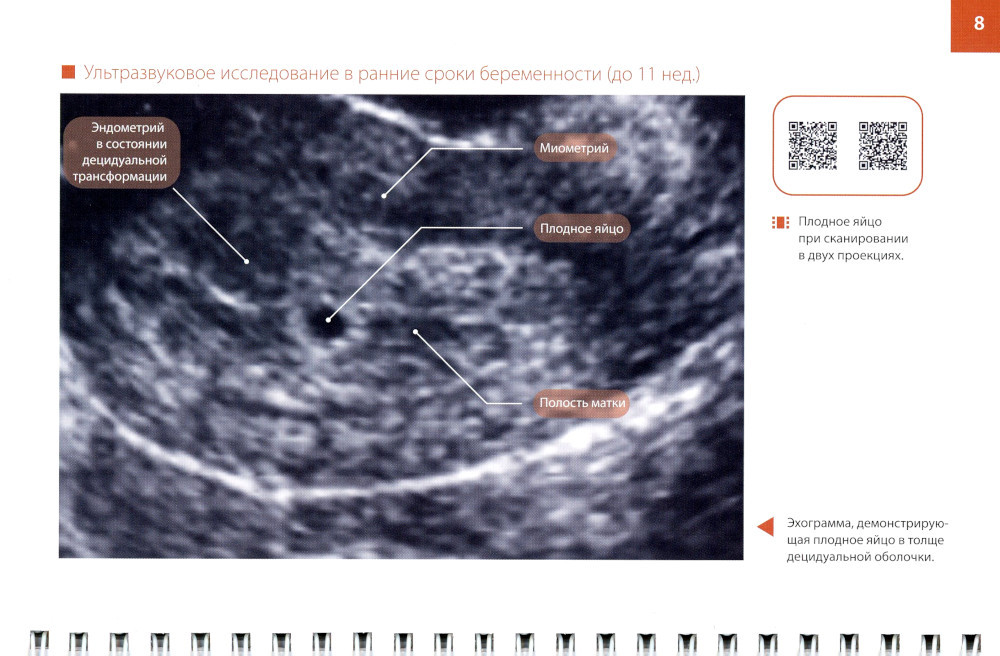

В книге обсуждаются возможности ультразвуковой визуализации различных структур плодного яйца в процессе нормальной маточной беременности, приводятся признаки неблагополучия на всех этапах ее развития, демонстрируются возможности ультразвуковой диагностики некоторых врожденных аномалий в эмбриональном периоде, представлены рекомендуемые протоколы исследования. Описаны основные анатомические структуры, доступные для оценки на сроках беременности 11-14 нед., определены оптимальные сроки проведения исследования. Представлен оптимальный алгоритм оценки ультразвуковой топографической анатомии, включая маркеры хромосомных аномалий. Пособие предназначено для врачей ультразвуковой диагностики, специалистов пренатальной диагностики, акушеров-гинекологов, перинатологов, а также студентов и ординаторов медицинских вузов.| Издательство | МЕДпресс-информ |